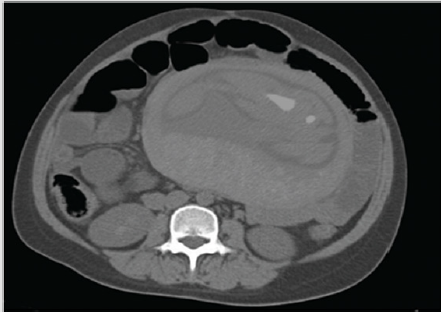

Essential in terms of assessing the staging of TNM in CRC, CT remains the subject of numerous debates. Of course, whenever the method can be avoided, it is good not to use this technique. If CT can be evocative for a diagnosis, especially in case of a major complication (Figure 3), or as a therapeutic guide, the practitioner should not hesitate to use it, the life of the mother being considered more valuable than that of the fetus (!). What can CT bring to the assessment of neoplasia during pregnancy? First of all, the method allows a three-dimensional evaluation of the colon-rectum relations with the adjacent structures. Secondly, the appreciation and demonstration of complications that are not apparent or lead to a rapid adverse evolution of the mother in the absence of a clear or obvious diagnosis, which puts her life in immediate danger, especially in the absence of rapid and effective treatment (perforations, obstructions, etc.) [145,146]. Third, an appreciation of staging. After an initial enthusiasm, in which CT was accredited with an accuracy of 85-90% in assessing the T index from TNM staging, high-rigorous studies [146-149] proved a much lower rate, between 50-70%, dependent of the lesion stage (the accuracy for the T4 lesion is much better compared to that of T2 or T3).

.Figure 3: Pregnant CT scan showing an occlusive complication of a recto-sigmoid junction CRC (collection of the clinic).